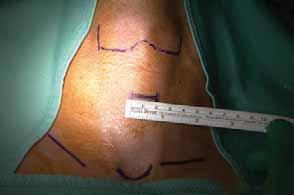

Rycina 76.15.

Rycina 76.16.

spod pachy

otoczki piersi

BABA